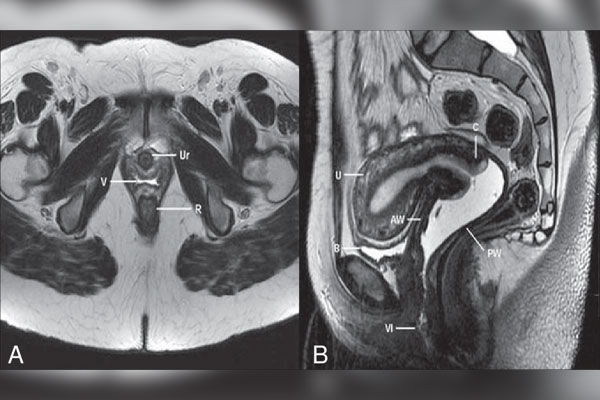

نوبت دهی ام آر آی رحم و اطلاعات آن

ام آر آی رحم برای ایجاد تصاویر با کیفیت بالا و دقیق از رحم و اندام های مجاور آن استفاده میشود. این روش می تواند به بررسی...